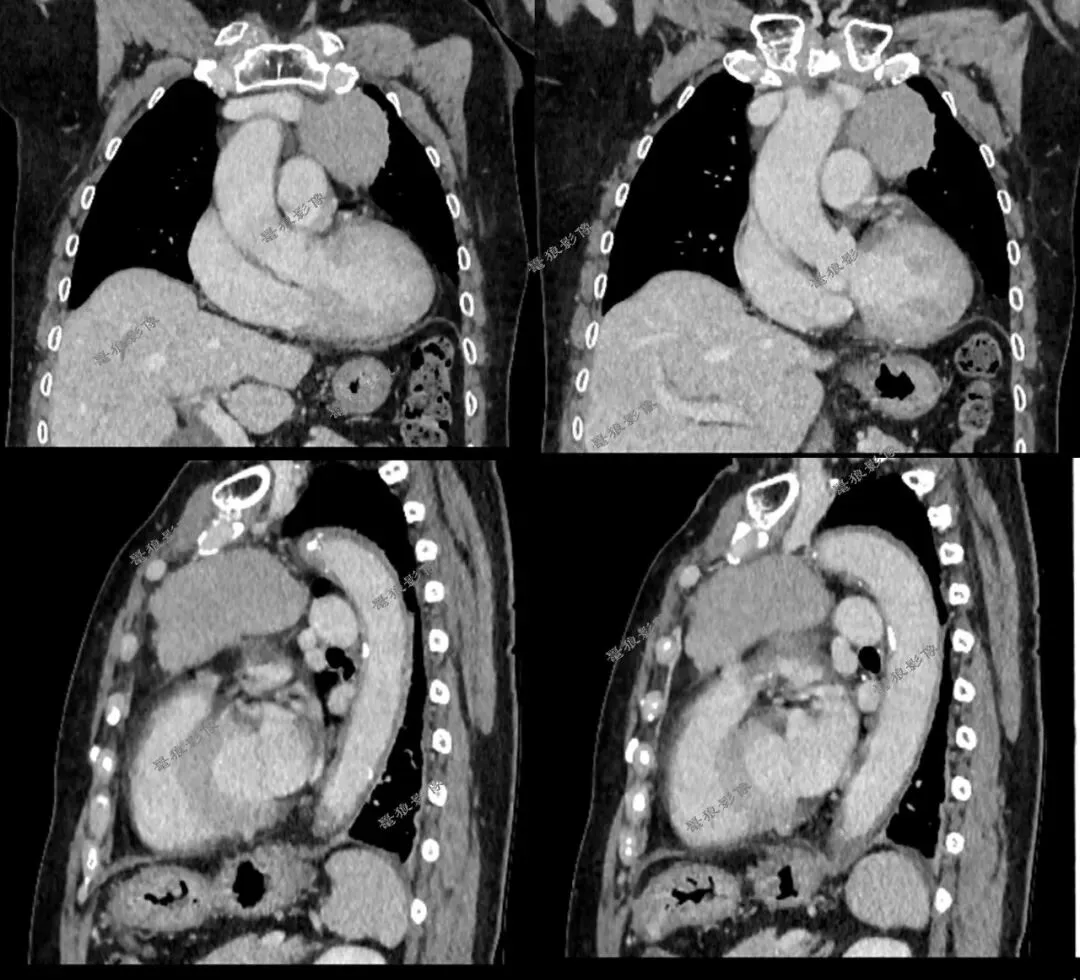

二、后行胸部CT平扫+增强(如下图):

胸部CT平扫+增强提示:

右肺下叶背段(IM118)见一浅分叶状实性结节,大小约为17mm×14mm,病灶边缘可见多发短毛刺,邻近斜裂稍凹陷,增强扫描病灶呈较明显不均匀强化。左前上纵隔见一类圆形软组织肿块,边界尚清,大小约69mm×44mm×51mm,密度较均匀,增强扫描病灶呈较均匀性轻度强化。

1.右肺下叶背段浅分叶状实性结节,考虑肺Ca可能性大,建议治疗后复查。

2.左前上纵隔软组织肿块,考虑胸腺瘤,必要时进一步检查以除外其它肿瘤性病变。